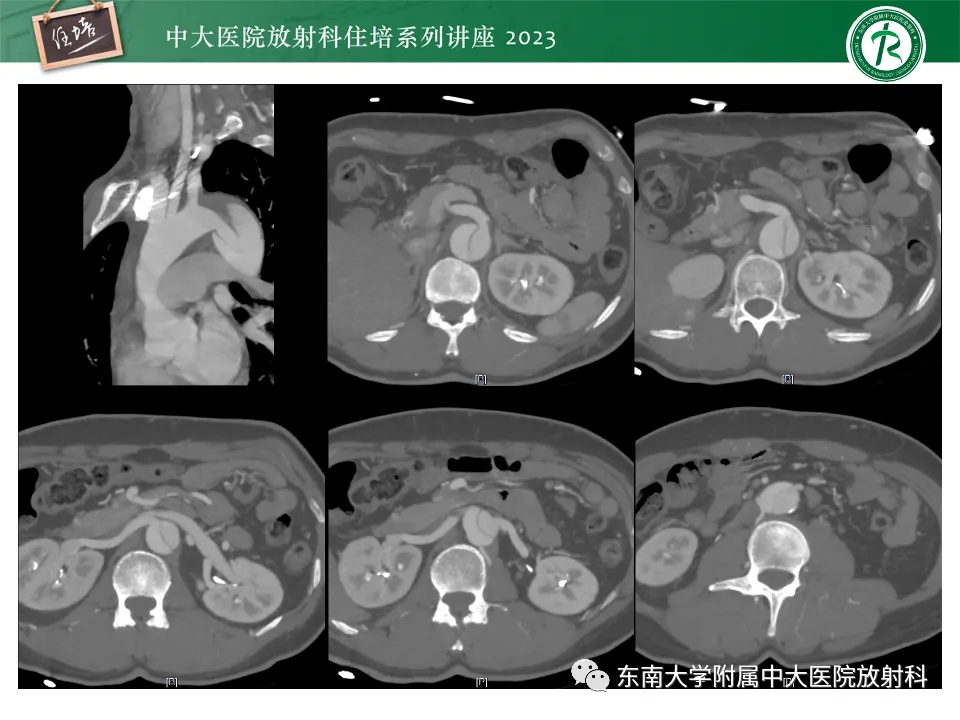

>精美课件丨心脏大血管常见疾病CT图像后处理要点

精美课件丨心脏大血管常见疾病CT图像后处理要点

来源:东南大学附属中大医院医学影像科